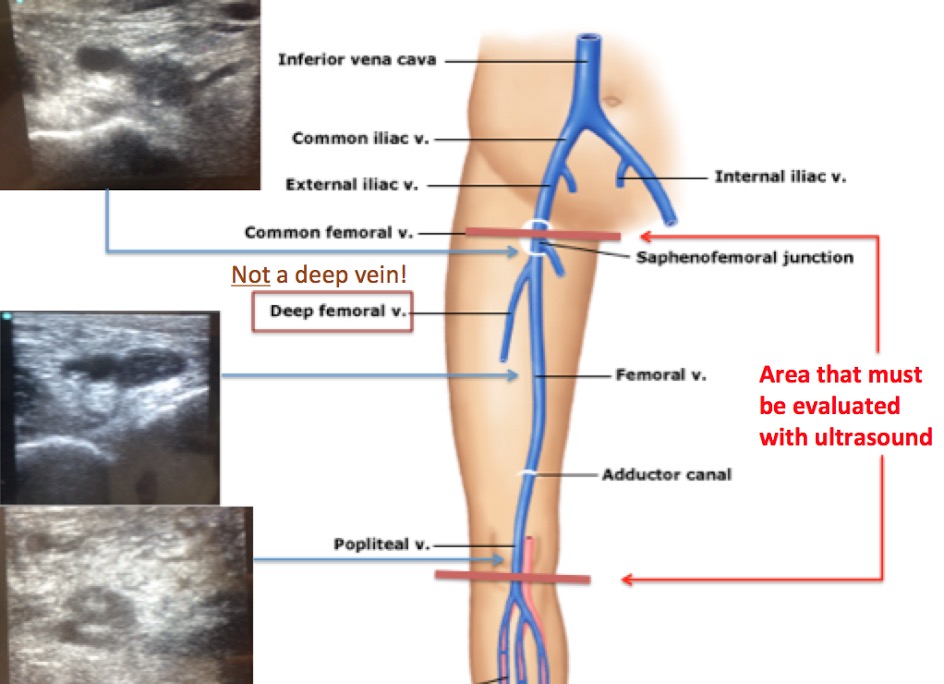

dvt ultrasound vein artery lower large study start vascular probe

vein dvt popliteal thrombosis artery compression

venous dvt deep thrombosis lower extremity system evlt

vein thrombosis deep venous thromboembolism treatment prevention femoral common thrombus distal proximal knee ppt secondary powerpoint presentation